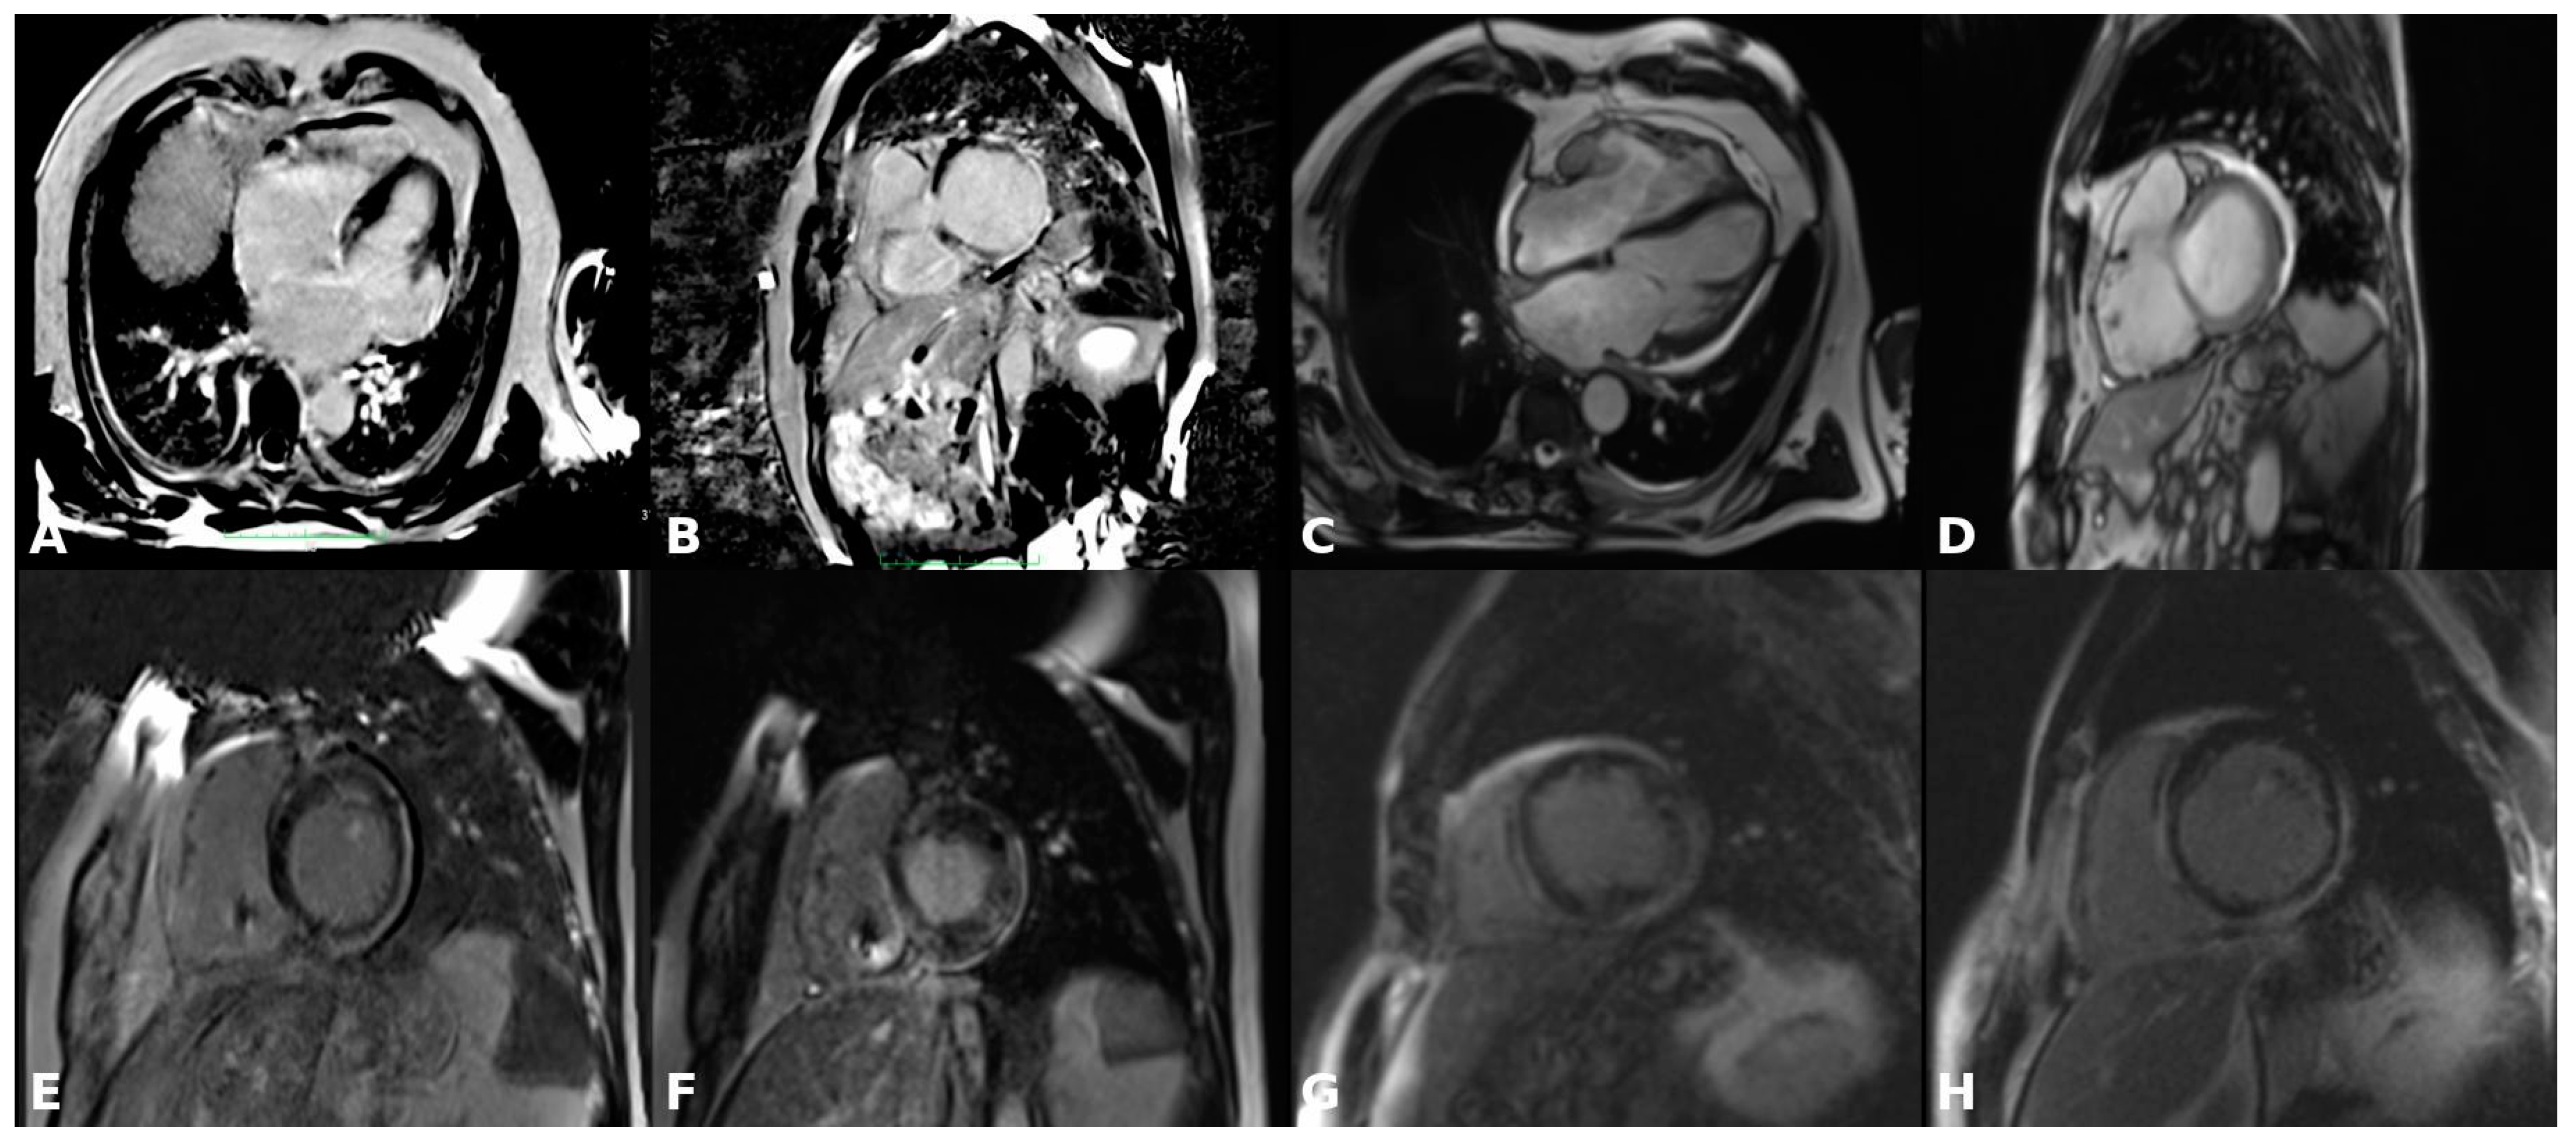

4.1. Late Gadolinium Enhancement Magnetic Resonance Imaging (LGE-MRI)